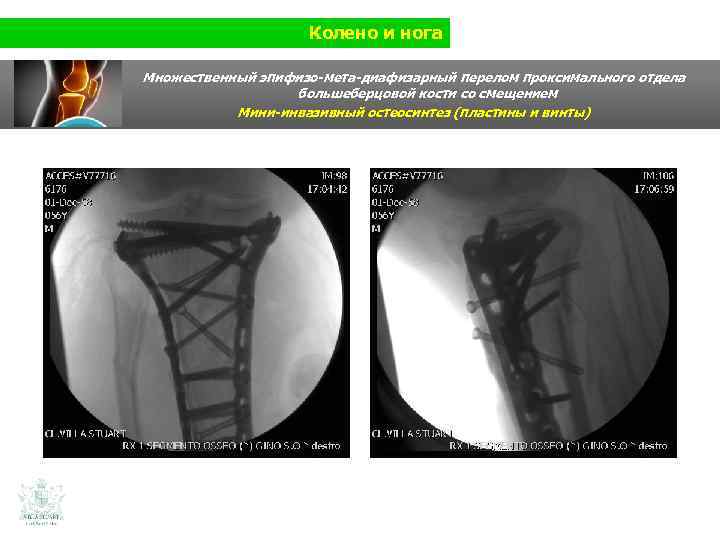

Колено и нога Множественный эпифизо-мета-диафизарный перелом проксимального отдела большеберцовой кости со смещением (Shatzer 6) Мини-инвазивный остеосинтез ( пластины и винты)

Колено и нога Множественный эпифизо-мета-диафизарный перелом проксимального отдела большеберцовой кости со смещением Мини-инвазивный остеосинтез ( пластины и винты)

Колено и нога Множественный эпифизо-мета-диафизарный перелом проксимального отдела большеберцовой кости со смещением Мини-инвазивный остеосинтез (пластины и винты)